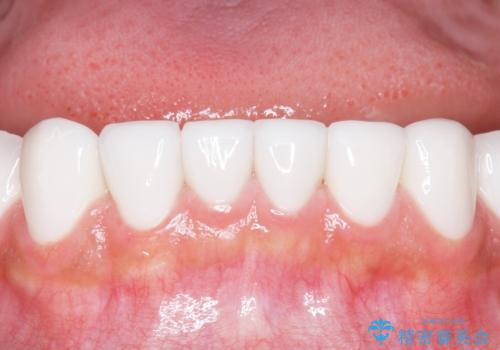

憧れのヴィジュアル系バンドマンのような白い歯になり、喜んで下さいました。

不適なレジン充填によるデコボコがなくなったことで歯磨きしやすくなり、また気にされていた咬み合わせも良くなり、ご満足頂けました。

クラウンの種類:オールセラミッククラウン スタンダード

シェード:NW0